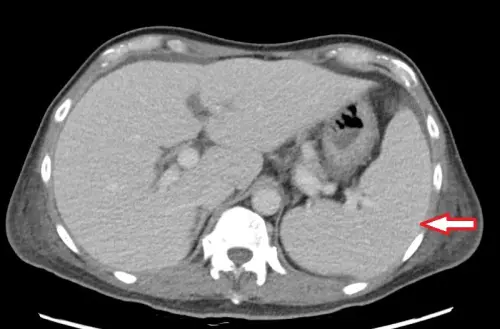

台北慈濟醫院心臟血管外科醫師楊凱文提到,個案抽血檢查顯示白血球、血小板及血紅素低下,必須輸血,但血液及骨髓等相關檢查均找不到病因,僅電腦斷層意外發現脾臟腫大與腹水。

▲醫師提醒,民眾若出現長期不明原因水腫、疲倦、反覆發燒等症狀,應積極就醫評估是否有心臟疾病的問題,排除感染可能。(圖/台北慈濟醫院提供) 長期出現3症狀 醫:盡快評估心臟病問題